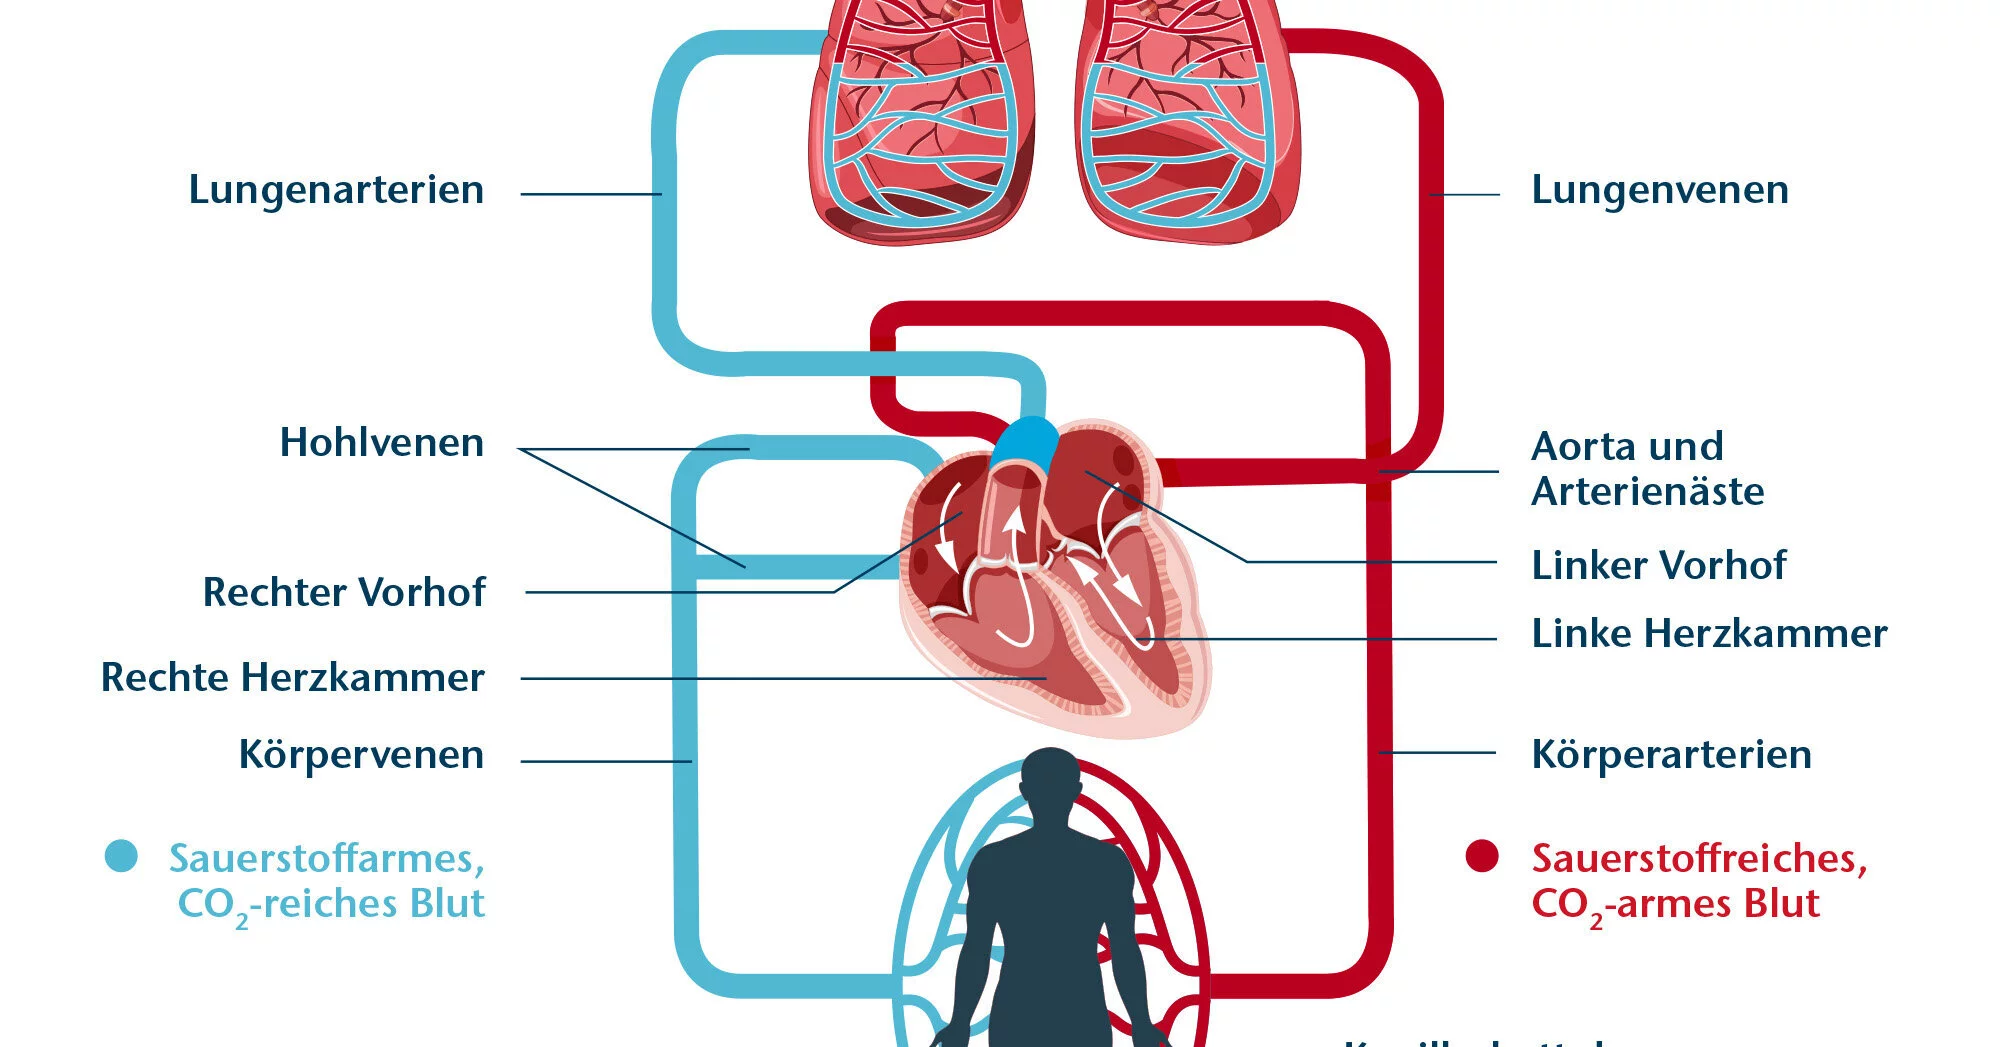

Die Pumpleistung ist die Menge des Blutes, die das Herz innerhalb einer bestimmten Zeit in den Blutkreislauf pumpt. Das gesunde Herz eines erwachsenen Menschen pumpt in Ruhe etwa 5 bis 6 Liter pro Minute. Bei einer körperlichen Belastung steigt dieses Herzminutenvolumen auf 20 bis 25 Liter. Krankheiten können die Pumpleistung des Herzens unnatürlich senken oder steigern.. In jeder Minute wird so einmal die gesamte Blutmenge – beim Erwachsenen fünf bis sechs Liter – durch den Körper befördert. Doch wie schafft das Herz jeden Tag diese Schwerstarbeit und wie funktioniert diese menschliche Pumpe? Herz-Kreislauf-System: So fließt das Blut. Das Herz ist das Zentrum des Blutkreislaufs.

Das Herzzeitvolumen (HZV, englisch cardiac output CO) ist das Volumen des Blutes, das pro Zeitspanne vom Herzen gepumpt wird (Volumenstrom).Die übliche Maßeinheit in der Humanmedizin ist Liter pro Minute, wobei dann vom Herzminutenvolumen (HMV), früher auch Minutenvolumen des Herzens, gesprochen wird.. Das Herzzeitvolumen ist ein Maß für die Pumpleistung des Herzens bezüglich der.. Der venöse Rückstrom zum Herzen bestimmt ganz wesentlich, wie viel Blut das Herz jede Minute auswirft. Abhängig von diesem Rückfluss pumpt das Herz automatisch das zurückströmende Blut in den Körperkreislauf. Je mehr Blut zurückströmt, desto mehr Blut wird vom Herzen ausgeworfen und umgekehrt.